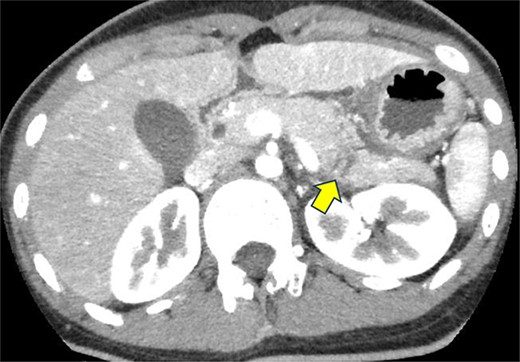

A 19-year-old woman who had fallen from a bicycle and bruised her upper left abdomen with handlebars presented to our emergency department 18 h after the injury with persistent abdominal pain. She was admitted with a diagnosis of pancreatic injury, as evidenced by elevated pancreatic amylase (P-Amy) levels (779 IU/L) and contrast-enhanced computed tomography (CT) showing a linear area with poor contrast in the pancreatic body (Fig. 1). Physical examination revealed a flat abdomen with mild tenderness in the upper left quadrant. Biochemical blood tests revealed elevated inflammatory markers; white blood cell count 10 950/μl, and C-reactive protein 0.58 mg/dl. On the fourth day, white blood cell count elevated to 21 940/μl and C-reactive protein elevated to 32.7 mg/dl. Contrast-enhanced CT revealed fluid accumulation, indicating pancreatic pseudocyst, primarily in the ventral pancreatic body and extending toward the spleen, along with edematous thickening of the adjacent stomach wall (Fig. 2).

Contrast-enhanced CT of the abdomen on the fourth day. Fluid accumulation (pancreatic pseudocyst) was observed, primarily located on the ventral pancreatic body and extending toward the vicinity of the spleen, along with edematous thickening of the adjacent gastric posterior wall.